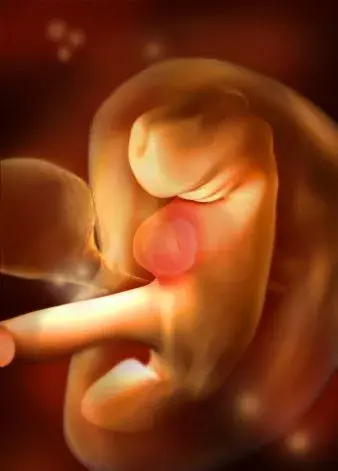

胎兒長到1.66厘米,胎形已定,可分出胎頭、體及四肢,胎頭大于軀干。B超可見胎囊約占官腔1/2,胎兒形態及胎動清楚可見,并可看見卵黃囊。器官已有明顯的特征,手指和腳趾間有少量的蹼狀物。胚胎的各種復雜的器官都開始成長,牙和腭開始發育,耳朵在繼續成形,胎兒的皮膚很薄,血管清晰可見。胚胎開始有運動。

胎兒長到2.15厘米,胎兒頭大于胎體,各部表現更清晰,頭顱開始鈣化、胎盤開始發育。B超可見胎囊幾乎占滿宮腔,胎兒輪廓更清晰,胎盤開始出現。胎兒所有的器官、肌肉、神經都開始工作,并且發育迅速。手部從手腕開始變得稍微有些彎曲,雙腳開始擺脫蹼狀的外表,眼簾開始覆蓋住眼睛。